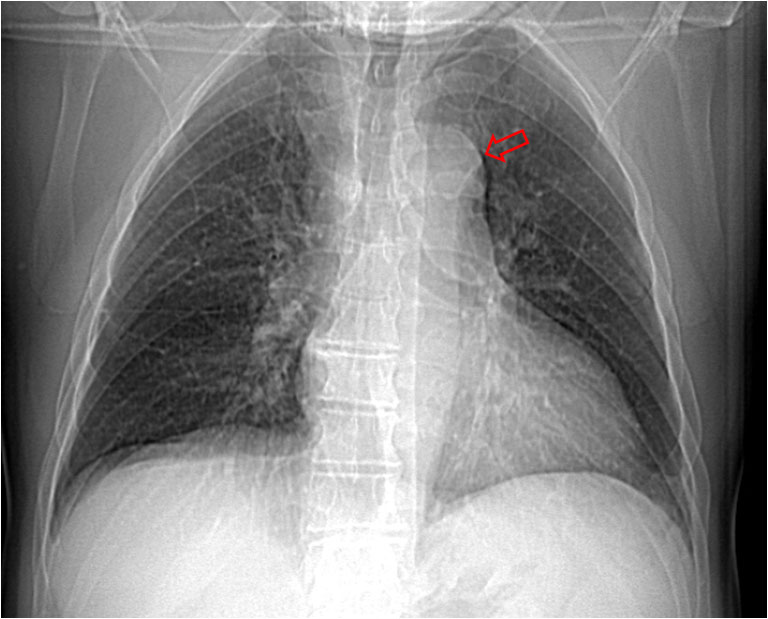

SIGNO DE FLEISHNER o DEL HILIO ABULTADO o DEL NUDILLO

En la radiografía posteroanterior o anteroposterior de tórax, la presencia de una arteria pulmonar agrandada puede indicar tromboembolismo, especialmente cuando no está presente en los estudios previos. Este signo también se llama signo de plump hilus o Signo del nudillo.

En el corte del angioTC de tórax con contraste del mismo paciente, vemos un aumento de tamaño de la arteria pulmonar, que presenta un defecto de repleción (flecha) correspondiente al tromboembolismo.